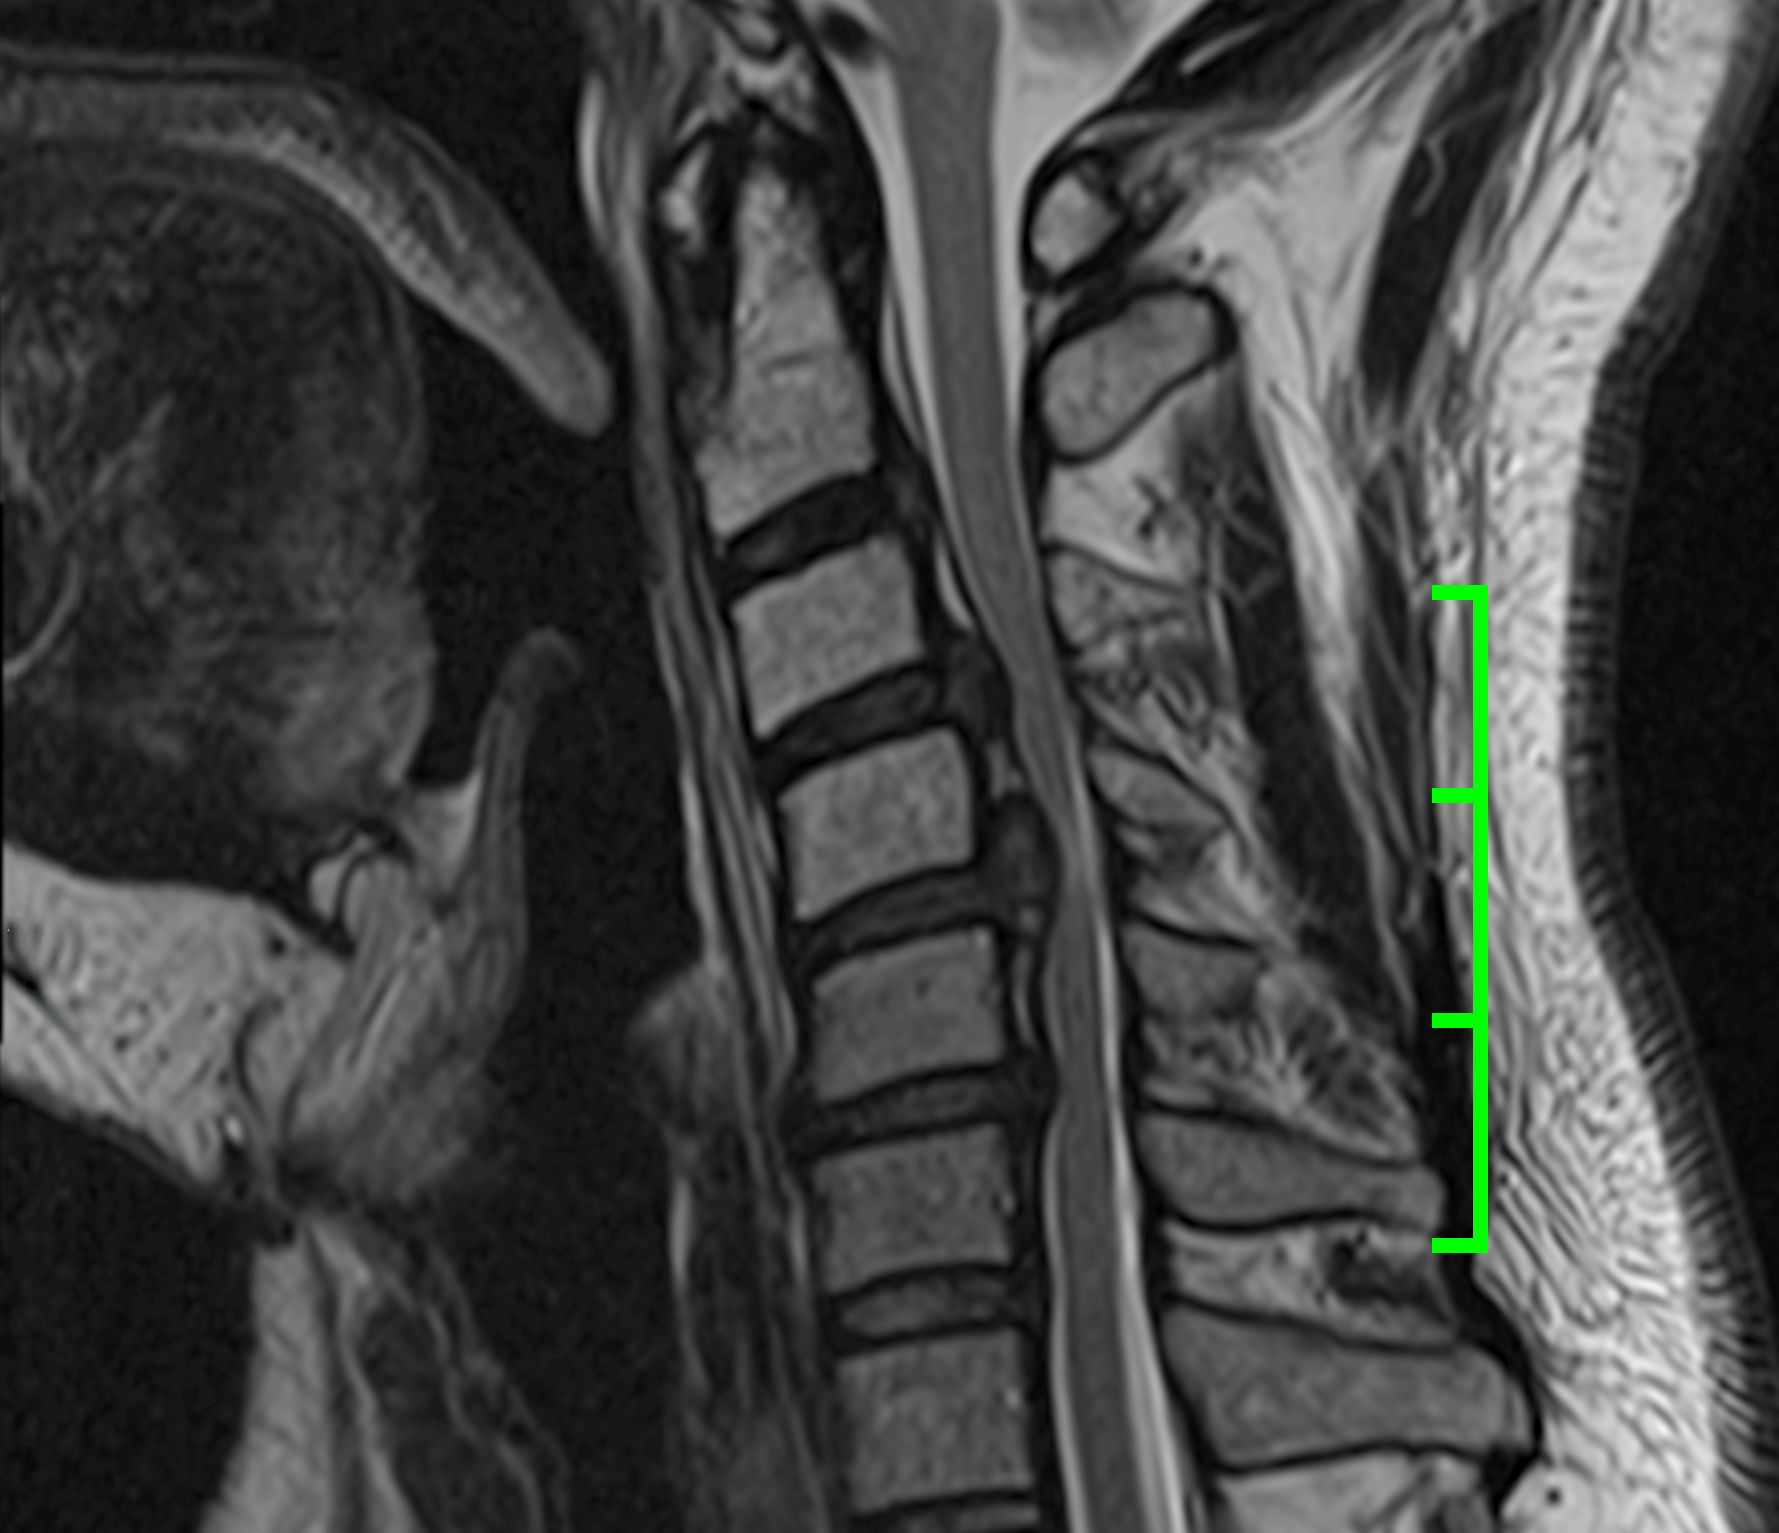

I have a serious spinal cord injury. In one spot, my spinal cord is compressed by more than fifty percent. On January 5th, I will undergo a six-hour operation to remove the vertebral arches from C3 to C6, decompress my spine, and fuse my neck with rods and screws.

The surgery is complicated by the fact that I had 38 radiation treatments to my neck twenty years ago when I was fighting stage IV cancer. Radiated tissue doesn't heal the same way, so there are very serious risks. But without the surgery, permanent paralysis is all but guaranteed.